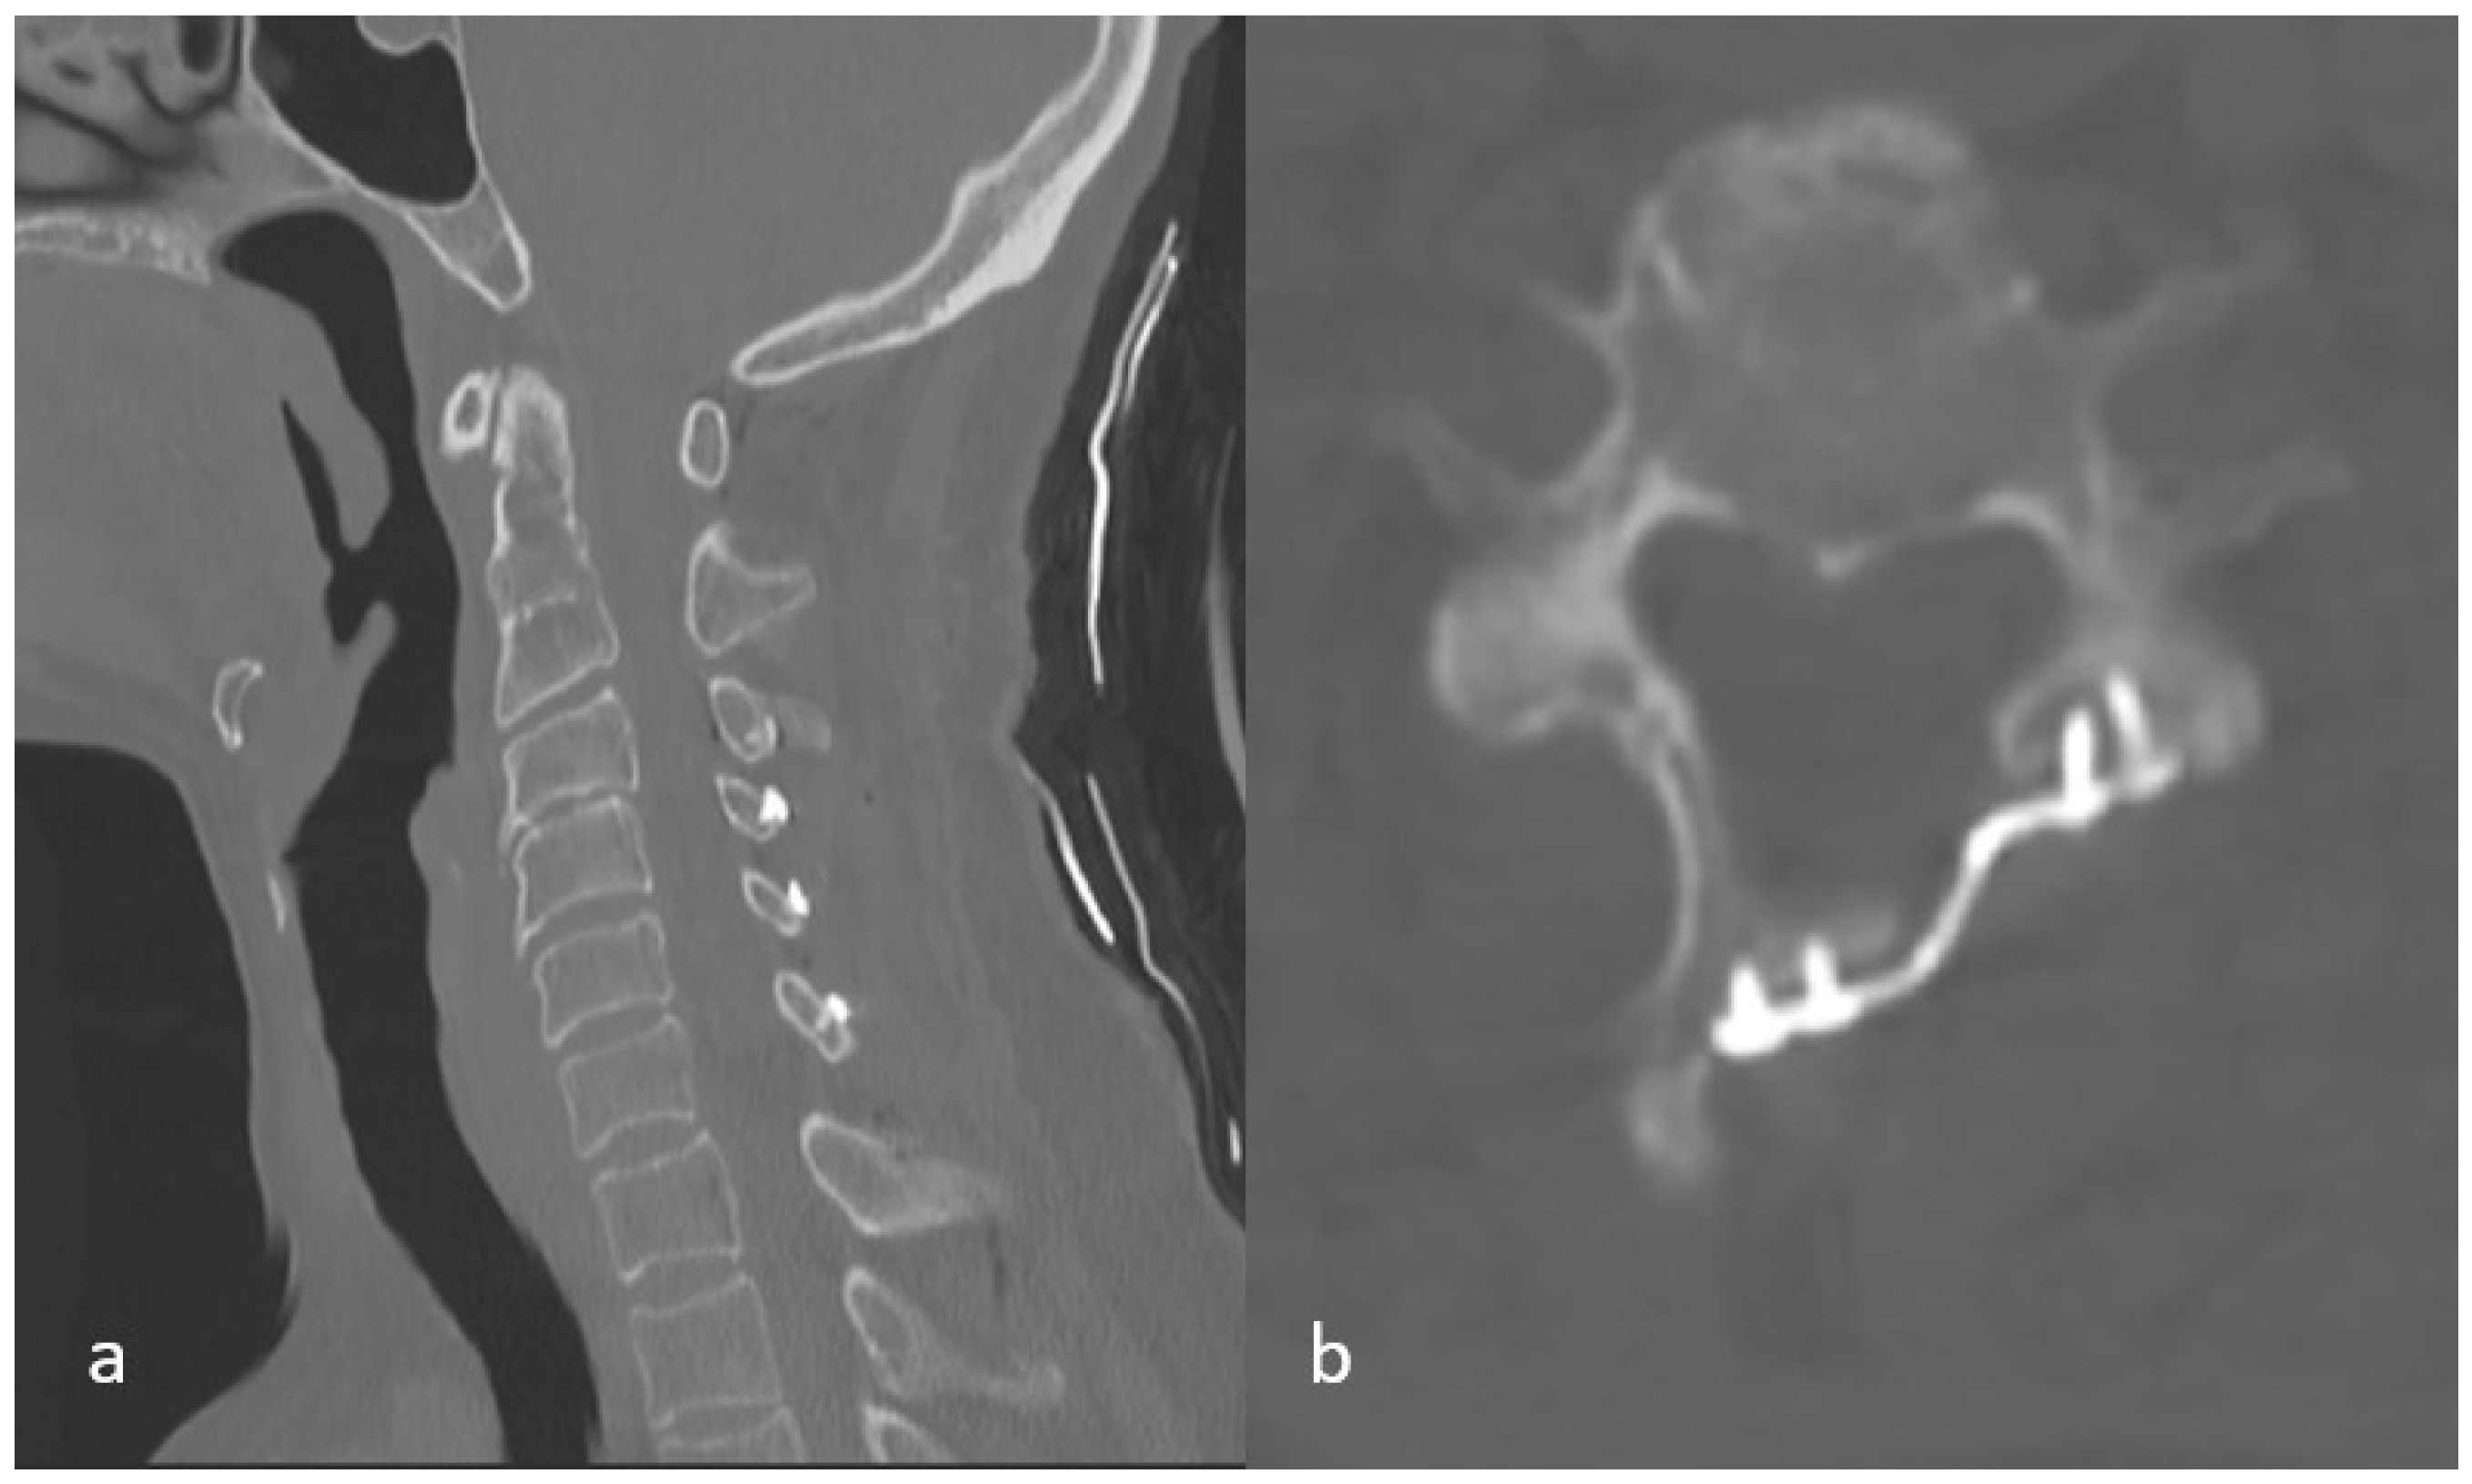

2.2.4. Independent Variables Detected on Early Postoperative CT Imaging

- Whether there is a lamina fracture or not

- Total number of lamina fractures

- Whether or not there is a fracture at the highest level where laminoplasty was performed

- Whether any of the screw placed in the lateral mass causes facet joint disturbance or not (Figure 6),

- Number of facet disturbance,

- Whether there is uppermost facet disturbance or not,

- Whether there is lowermost facet disturbance or not